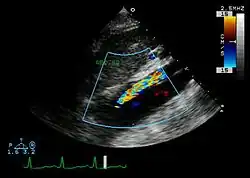

Ultrasound

The transesophageal echocardiogram (TEE) is a good test in the diagnosis of aortic dissection, with a sensitivity up to 98% and a specificity up to 97%. It has become the preferred imaging modality for suspected aortic dissection. It is a relatively noninvasive test, requiring the individual to swallow the echocardiography probe. It is especially good in the evaluation of AI in the setting of ascending aortic dissection and to determine whether the ostia (origins) of the coronary arteries are involved. While many institutions give sedation during transesophageal echocardiography for added patient comfort, it can be performed in cooperative individuals without the use of sedation. Disadvantages of TEE include the inability to visualize the distal ascending aorta (the beginning of the aortic arch), and the descending abdominal aorta that lies below the stomach. A TEE may be technically difficult to perform in individuals with esophageal strictures or varices.

Type A aortic dissection[36]